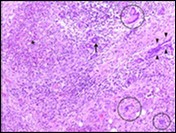

Figure 3.Granulomatous mastitis with scattered langhans and foreign body giant cells, epitheloid cell granuloma and lymphoid ingress11.

Core needle biopsy of idiopathic granulomatous mastitis enunciates multiple aggregates of non- caseating epitheloid cell granulomas within and encompassing breast lobules, constituted of epitheloid histiocytes, lymphocytes, neutrophils and multinucleated giant cells. Granulomatous inflammation is predominantly lobulo-centric. The inflammation is preponderantly composed of lymphocytes, plasma cells, epitheloid histiocytes, multinucleated giant cells and neutrophils. Neutrophils can configure micro-abscesses and encompass vacant micro-cystic cavities, morphological features which are in common with cystic neutrophilic granulomatous mastitis. Non specific lobulitis along with a lymphoid and plasma cell infiltrate accompanies the granulomatous inflammation. Necrosis is usually absent. Neutrophilic micro-abscesses can be accompanied by fistula formation 4, 5.

Multinucleated giant cells are detected in an estimated three fourths (78.5%) instances. Plasma cells are discernible in around half (53.9%) of the subjects and usually appear at the margins of cystic vacuoles with centric accumulation of neutrophils within the granulomas.